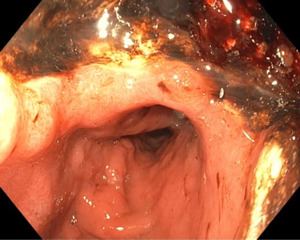

Esophagogastroduodenoscopy (EGD) demonstrated a large gastric ulcer with a necrotic base involving most of the lesser curvature (Figure 2). There was also luminal narrowing and mucosal friability extending from the mid-esophagus to the gastroesophageal junction. Biopsies from both sites showed infiltration by poorly differentiated cells with hyperchromatic, angulated nuclei, nuclear molding, and minimal cytoplasm. Immunohistochemistry was positive for AE1/AE3, synaptophysin, and chromogranin, and negative for TTF1, CD3, and CD20, confirming neuroendocrine and epithelial differentiation. The Ki-67 proliferation index exceeded 80%, consistent with a high-grade tumor (Figure 3). These findings supported a diagnosis of pure small cell neuroendocrine carcinoma (SCNEC). Cytological analysis of pleural fluid obtained via thoracentesis revealed similar small cell morphology, confirming metastatic disease; however, no cytology image was available for publication.